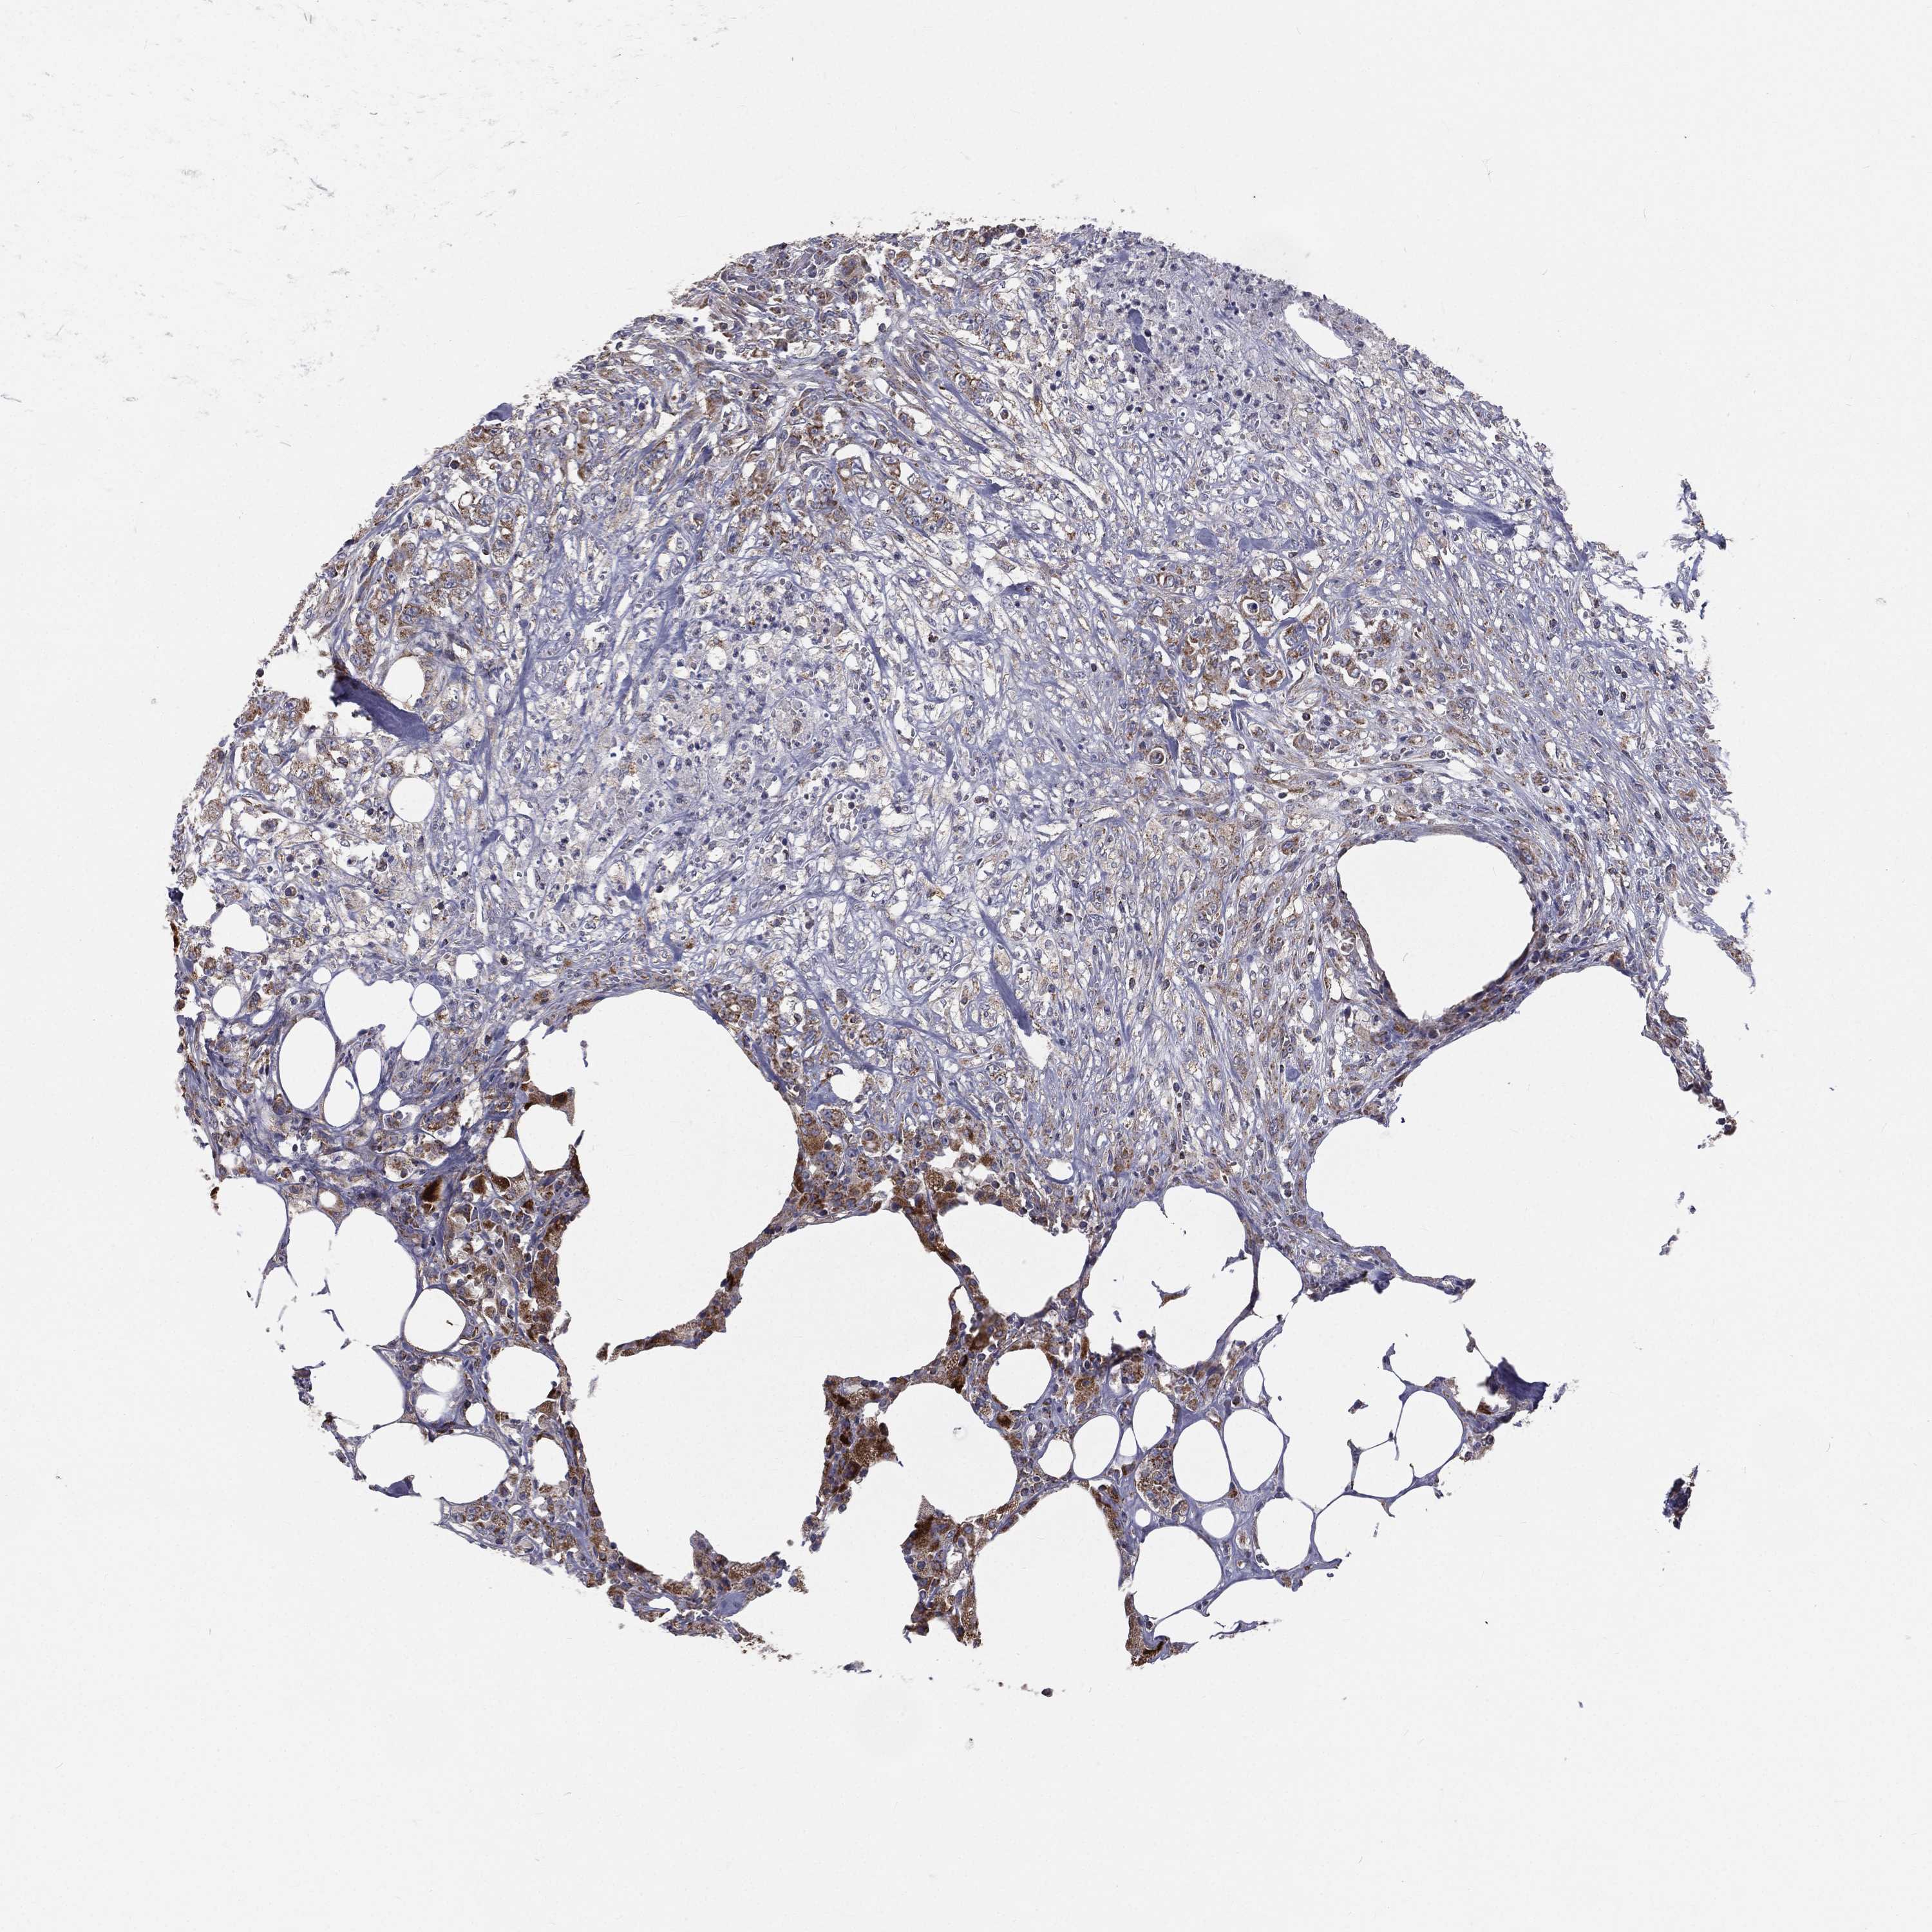

RECTUM ADENOCARCINOMA (TCGA) - Interactive survival scatter ploti

The Survival Scatter plot shows the clinical status (i.e. dead or alive) for all individuals in the patient cohort, based on the same data that underlies the corresponding Kaplan-Meier plots. Patients that are alive at last time for follow-up are shown in blue and patients who have died during the study are shown in red.

The x-axis shows the expression levels (FPKM) of the investigated gene in the tumor tissue at the time of diagnosis. The y-axis shows the follow-up time after diagnosis (years). Both axes are complimented with kernel density curves demonstrating the data density over the axes. The top density plot shows the expression levels (FPKM) distribution among dead (red) and alive patients (blue). The right density plot shows the data density of the survived years of dead patients with high and low expression levels respectively, stratified using the cutoff indicated by the vertical dashed line through the Survival Scatter plot. This cutoff is automatically defined based on the FPKM cutoff that minimizes the p-score. The cutoff can be changed by dragging the vertical line or by entering a cutoff value in the square labeled "Current cut-off".

Under the Survival Scatter plot the p-score landscape (black curve; left axis) is shown together with dead median separation (red curve; right axis). Dead median separation is the difference in median mRNA expression between patients who have died with high and low expression, respectively. It is calculated as follows: median FPKM expression of dead patients with high expression - median FPKM expression of dead patients with low expression. This is intended to aid the user in visually exploring custom cutoffs and the associated p-scores and dead median separation.

Individual patient data is displayed and can be filtered by clicking on one or more of the category buttons on the top of the page. Categories describing expression level and patient information include: high, low, alive, dead, female, male and tumor stages. The scale of the x-axis can be toggled between linear and log-scale by clicking on the "x log" button. Mouse-over function shows TCGA ID, patient information and mRNA expression (FPKM) for each patient.

& Survival analysisi

Kaplan-Meier plots summarize results from analysis of correlation between mRNA expression level and patient survival. Patients were divided based on level of expression into one of the two groups "low" (under cut off) or "high" (over cut off). X-axis shows time for survival (years) and y-axis shows the probability of survival, where 1.0 corresponds to 100 percent.

HADH is not prognostic in Rectum Adenocarcinoma (TCGA)

Best expression cut offi

Based on the FPKM value of each gene, patients were classified into two groups and association between prognosis (survival) and gene expression (FPKM) was examined. The best expression cut-off refers the FPKM value that yields maximal difference with regard to survival between the two groups at the lowest log-rank P-value. Best expression cut-off was selected based on survival analysis .

When clicking on this number, the vertical dashed line indicating cut-off, the interactive survival plot, and the Kaplan-Meier curve will be adjusted to show results based on the best expression cut-off.

: 70.91

P scorei

Log-rank P value for Kaplan-Meier plot showing results from analysis of correlation between mRNA expression level and patient survival.

N/A

TCGA RNA samplesi

RNA-seq data is reported as average FPKM (number Fragments Per Kilobase of exon per Million reads), generated by the The Cancer Genome Atlas (TCGA) .

Normal distribution across the dataset is visualized with box plots, shown as median and 25th and 75th percentiles. Points are displayed as outliers if they are above or below 1.5 times the interquartile range. FPKM values of the individual samples are presented next to the box plot.

Average pTPM 70.0

Number of samples 88